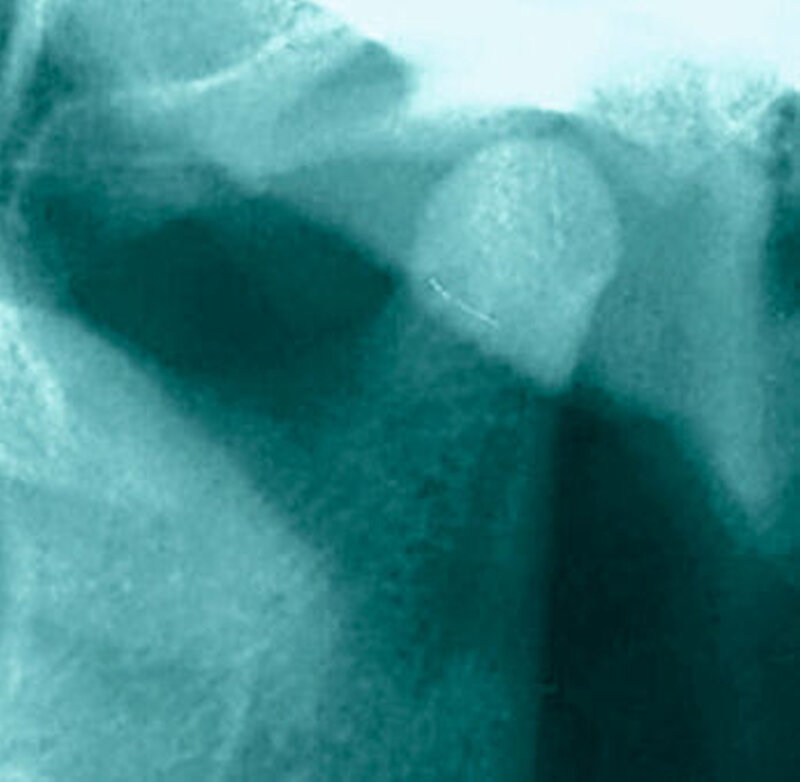

Bereits 2004 wies Carla Evans [Evans, 2005] auf das Risikomanagement bei Allgemeinerkrankungen hin und stellte am Beispiel der JIA dar, dass Unterkieferrücklagen und frontal offene Bisse aus der Kiefergelenkzerstörung entstehen können. Die Röntgenaufnahmen einer JIA-Patientin mit oligoartikulärer Form und Beteiligung des rechten Kiefergelenkes zeigen den typischen Verlauf sehr gut. Bei ursprünglich sehr dezenten Befunden, wie einer s-förmigen Mundöffnung von 44 mm, einer geringen Mittenabweichung um 2 mm nach rechts und einem frontal offenem Biss klagte sie über Schmerzen beim Essen, was den Anlass zur weiteren Diagnostik bot. Die erste Panoramaröntgenschichtaufnahme (Abbildung 1a-c) zeigt auf der rechten Seite einen abgeflachten Kondylus und eine bereits verstrichene Fossa condylaris. Ein Jahr später vermittelt das Fernröntgenseitenbild (Abbildung 1d) trotz fortschreitender kondylärer Resorption ein harmonisches Bild, während nach drei Jahren bei voranschreitendem Abbau des rechten Kondylus (Abbildung 1e) eine Rücklage der Mandibula und eine Bissöffnung manifest sind (Abbildung 1f).

Bei 152 durchschnittlich 12-jährigen Rheumapatienten wurden die kondyläre Morphologie und Symmetrie beziehungsweise Asymmetrie im Vergleich zu einer Kontrollgruppe anhand der OPG analysiert. Zur Analyse erfolgte die Zuordnung zu vier morphologischen Graden je Kondylus (Abbildung 3a-d). Bei 45 Prozent der Rheumapatienten waren morphologische Veränderungen im Rahmen kondylärer Resorption unterschiedlicher Ausprägung zu finden. Die „Kontrollpatienten“ ohne JIA zeigten nur zu 14 Prozent formatypische Kondylen. Der Unterschied zwischen den beiden Gruppen war signifikant. Daher sollte bei der Routineauswertung von Panoramaröntgenschichtaufnahmen auf diese Anzeichen geachtet werden, insbesondere auch unter dem Aspekt, dass laut Assaf [2011] durchschnittlich 4,3 Jahre zwischen Erstmanifestation der JIA und Erstvorstellung in der Rheumasprechstunde des UKE liegen.